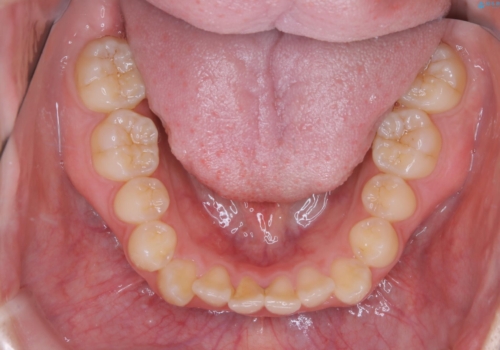

- 非抜歯、インビザライン治療希望の患者様です。

右の犬歯が八重歯になっており、通常であれば抜歯を選択する可能性が高くなりますが、

マイクロインプラントと呼ばれる骨に打ち込むネジを使用し、非抜歯での治療計画を立てました。